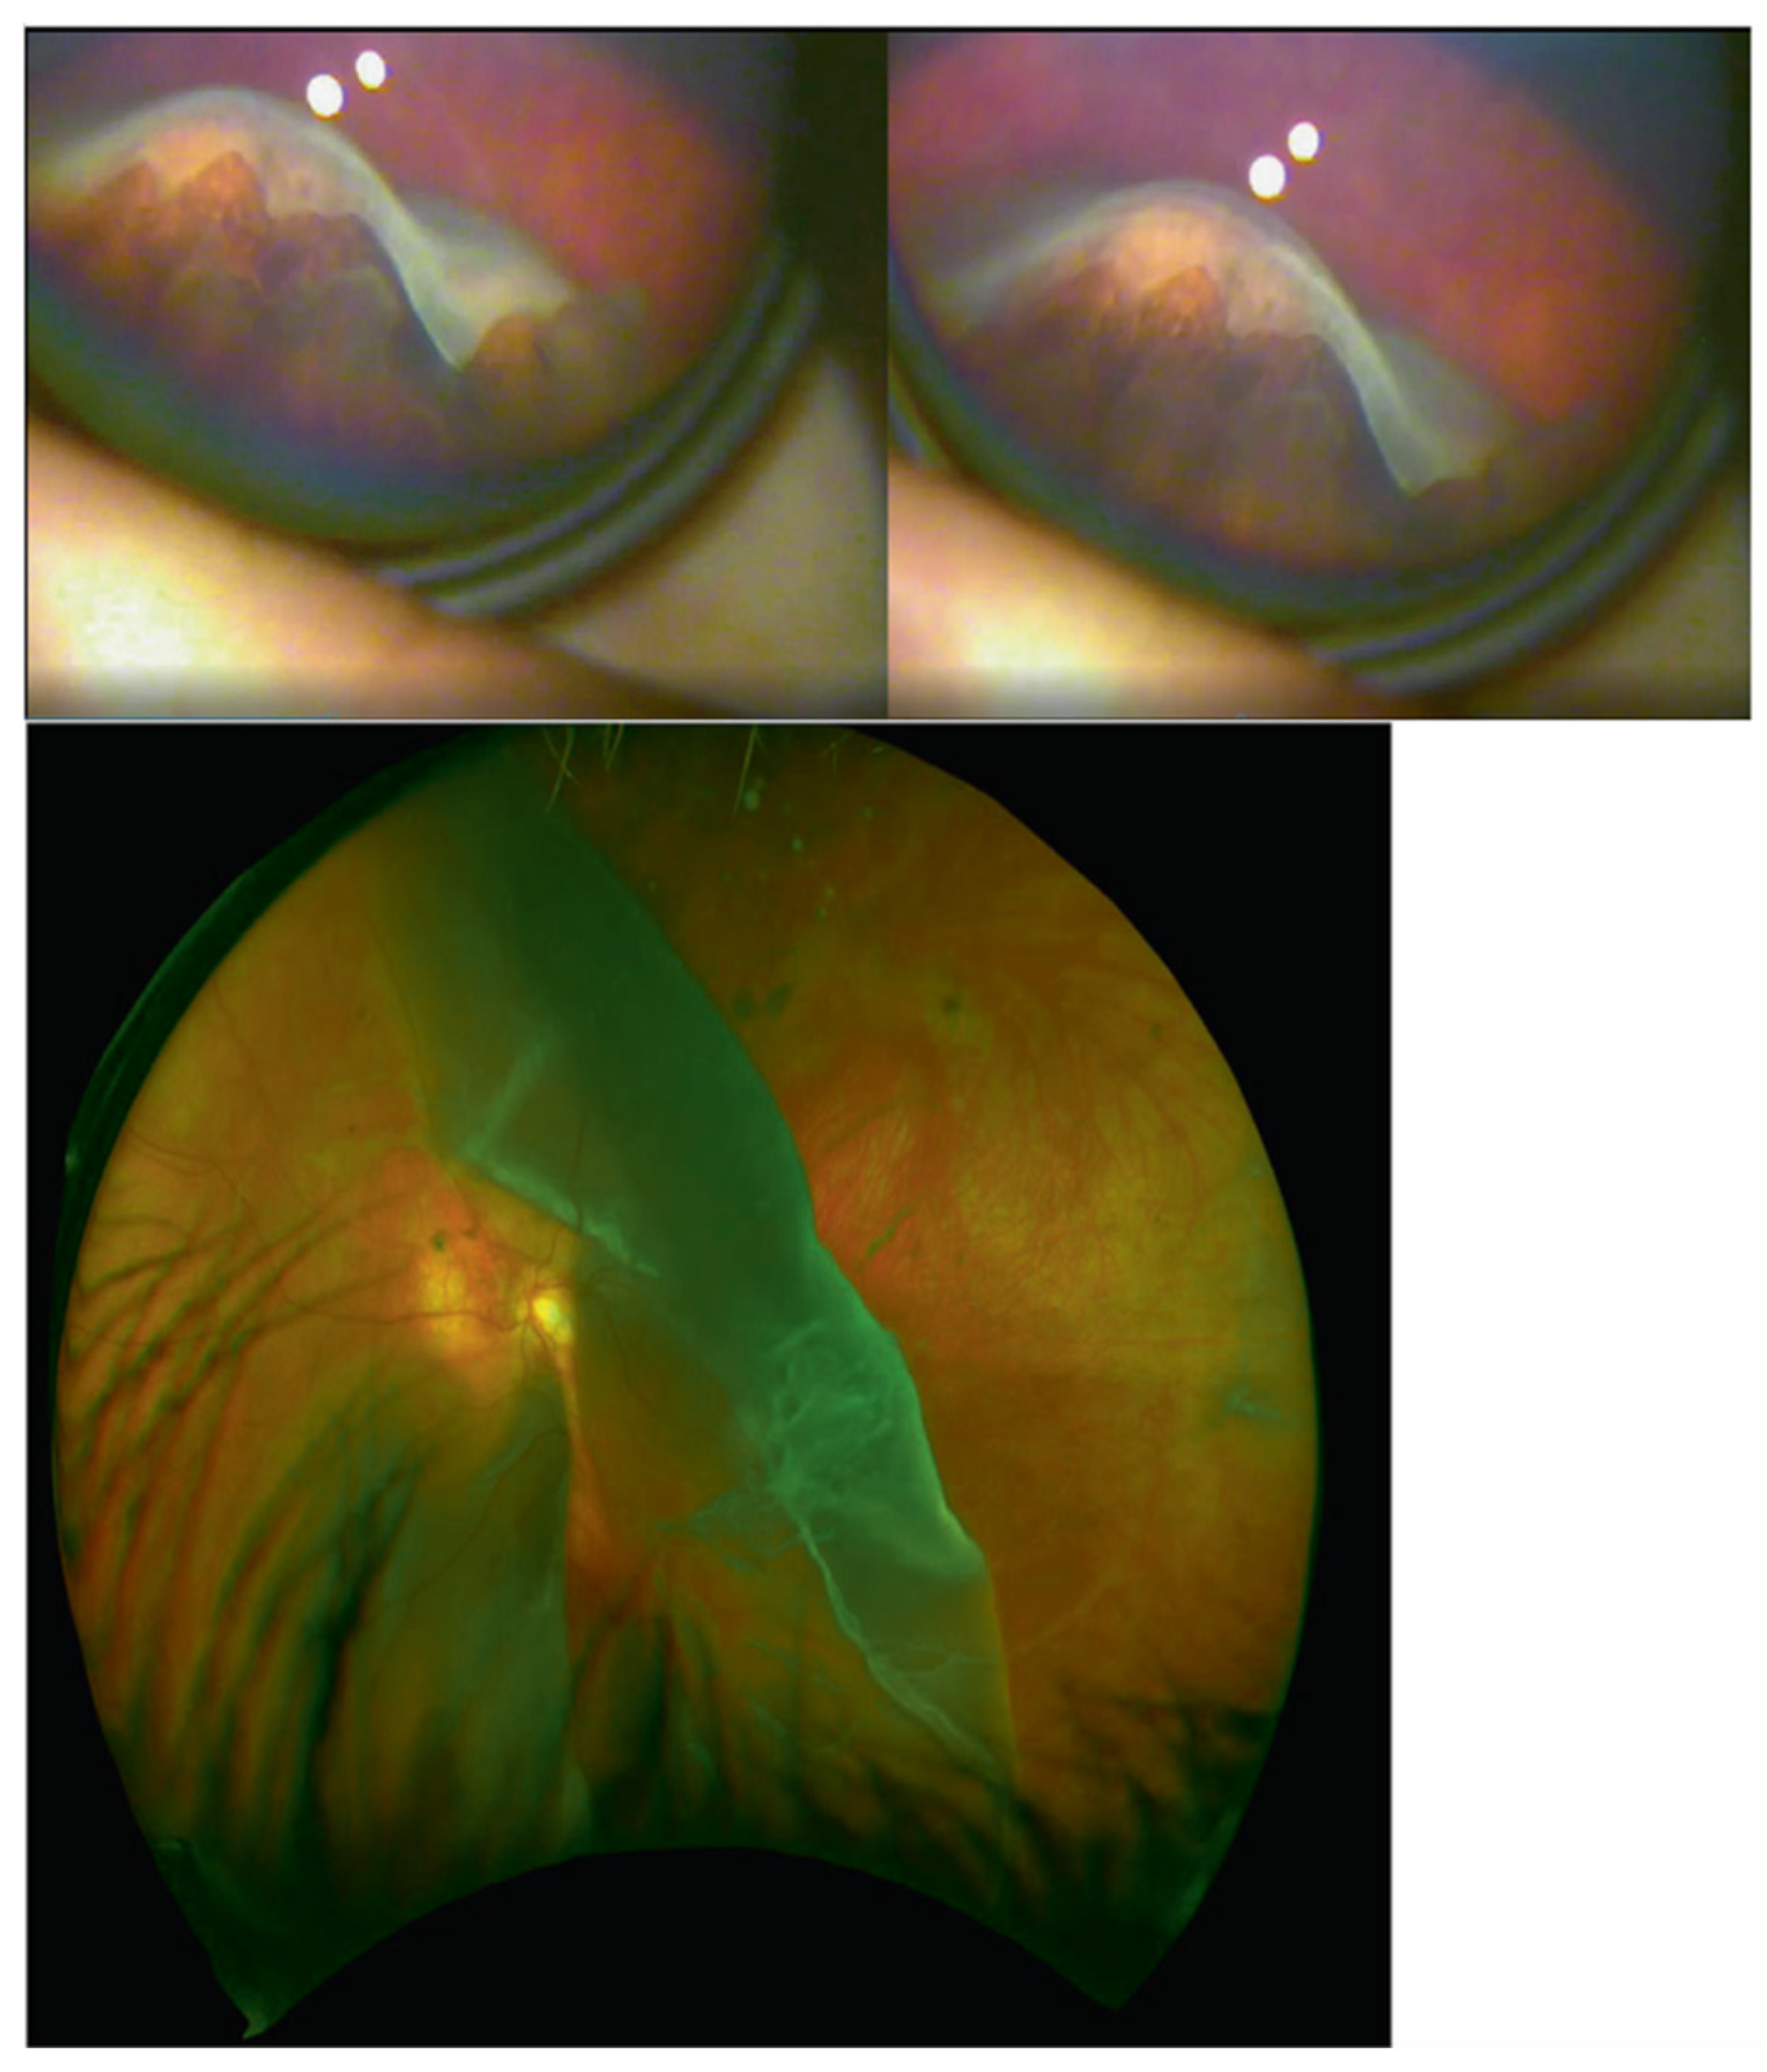

| Type 1 | COL2A1 | 12q13.11 | Type 1 membranous congenital vitreous anomaly, retinal detachment, congenital megalophthalmos, deafness, arthropathy, cleft palate. High risk of blindness | 108,300 |

| Type 2 | COL11A1 | 1p21.1 | Beaded type 2 congenital vitreous anomaly, retinal detachment, congenital megalophthalmos, deafness, arthropathy, cleft palate. | 604,841 |